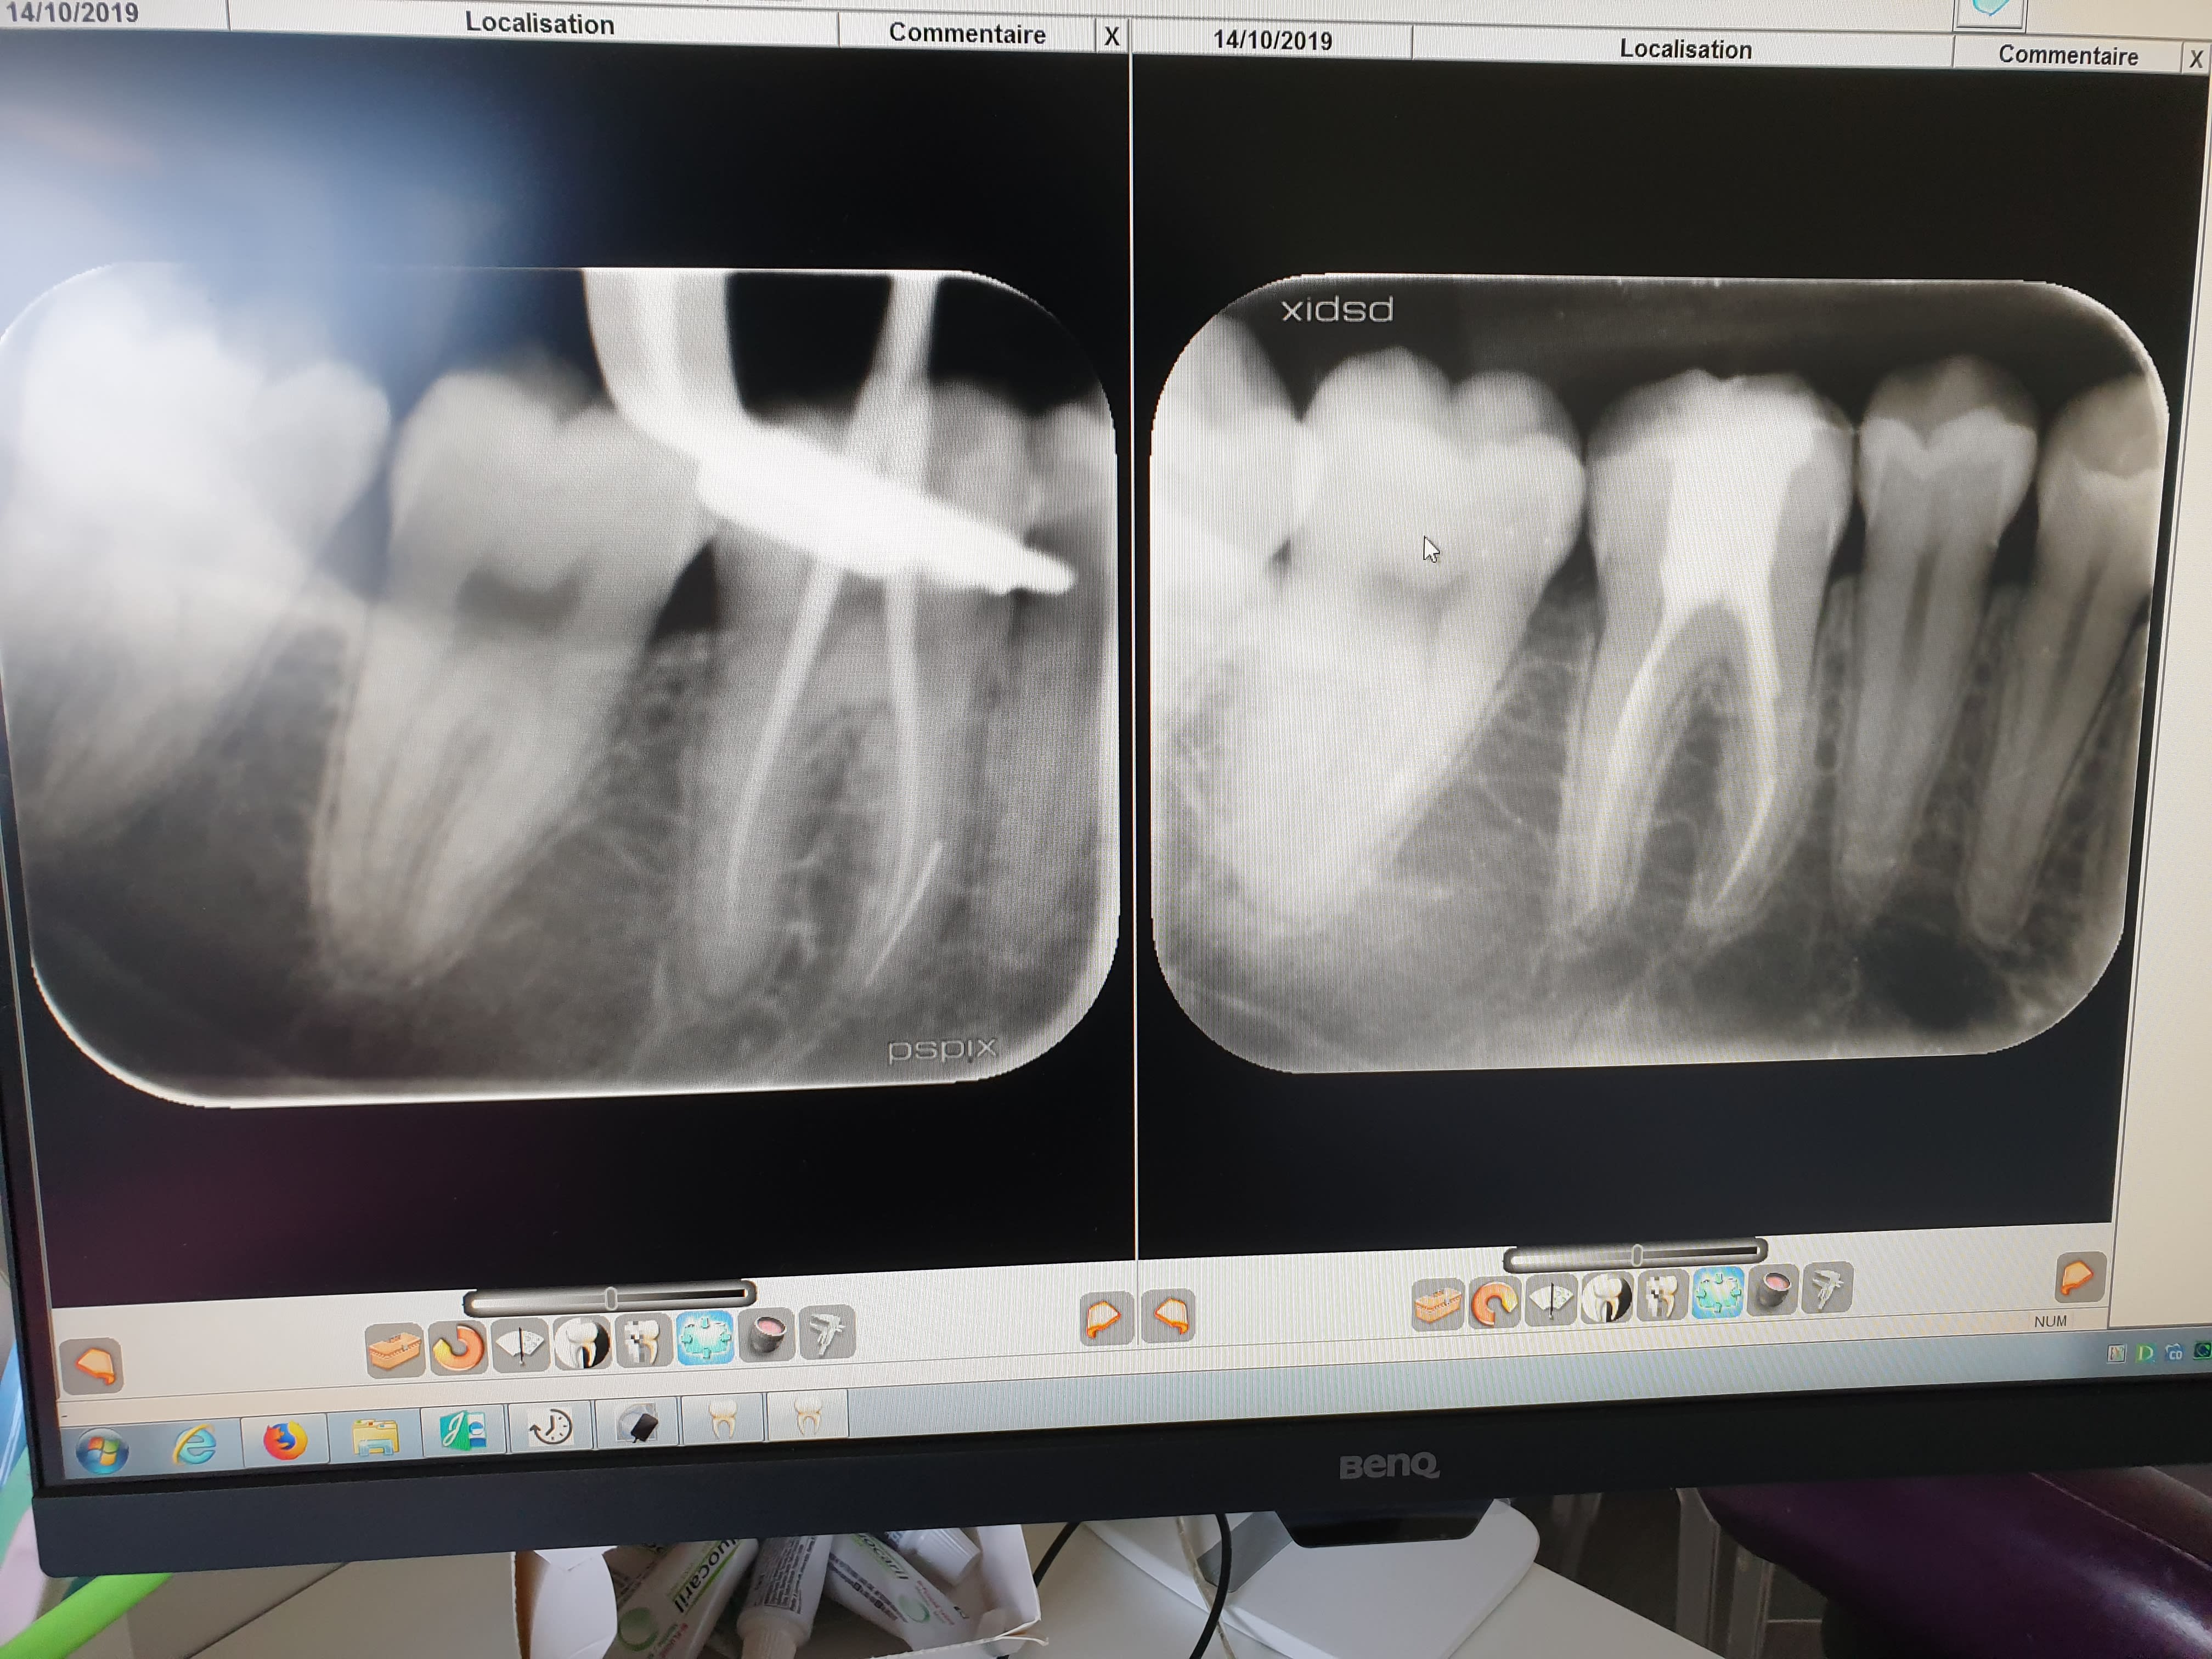

Lundi matin, dernière patiente de la matinée, j'ai fracturé mon instrument dans la racine MV d'une 46 sur une jeune de 23 ans... autant dire que ça me fait chier, surtout que c'est un beau morceau.

C'était en fin de trairement, j'avais beaucoup irrigué, sous digue, c'est l'instrument TS2 du 2shape.

Deja est-ce que c'est retirable selon vous ?

La patiente est au courant. En attendant j'ai posé un cone de gutta, j'ose pas trop obturer par par-dessus. Que feriez vous ?

1) tu essayes de le sortir en passant une lime fine mais si c’est serti, tu vas avoir du mal et le remède sera pire que le mal. A mon avis tu as un problème de cavité d’accès et ton instrument avait une courbure trop prononcée, radio initiale?

Vu la cavité d’accès je me suis dit la même chose .. peut être une grosse carie occlusale

D’où la première phrase de mon commentaire car la cavité d’accès me semble un peu réduite

C'est d'ailleurs la raison qui explique cette fracture instrumentale !!

L'axe ne parait pas si mauvais sur la radio mais il l'est très souvent dans le sens vestibulo-lingual, celui qu'on ne voit que sur un CBCT.